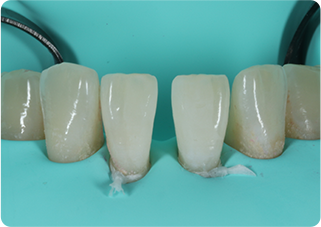

ダイレクトボンディング症例③ 正中離開

術前

ラバーダム防湿

術後

| 主訴 | 下の前歯の隙間が気になる |

|---|---|

| 治療期間/回数 | 2週間、3回 |

| 価格(税込) | 66,000円(税込) |

| リスク・副作用 | コンポジットレジンの破損、一時的な知覚過敏が生じる場合がある |

| ポイント | むし歯ではないので歯を削らずにダイレクトボンディングを行った。歯の形が理想の形になるよう、術前にシリコンインデックスを作成し充填の際に使用。また、充填時にラバーダム防湿を行うことで、詰め物の接着効果が最大限発揮できるようにした。 |